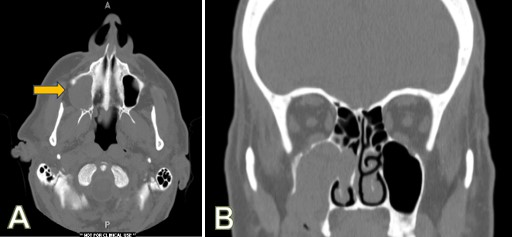

CT imaging showed that the expansile mass consisted of soft tissue which had destroyed the facial cortex of the right maxillary alveolus, destroyed the right maxillary sinus bony floor and lateral wall, and completely filled the sinus. It also had perforated through the medial wall of the sinus to fill much of the right nasal sinus, extending superiorly into the ethmoid region (Figure 2). The infraorbital bone at the top of the maxillary sinus also appeared to be partially destroyed.

Figure 2: CT radiographic appearance. (A) Transverse view showing destruction of the right maxillary lateral sinus wall (arrow) and the posterior wall, with tumor completely filling the sinus and extending into the pterygomaxillary space; (B) Coronal view showing destruction of the medial sinus wall with extension of tumor into right nostril, the overlying ethmoid sinus, and with partial destruction of the infraorbital or superior maxilla on the right.